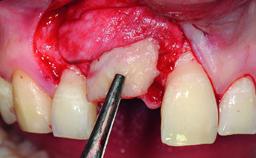

A 30-year-old patient presented at our clinic with a chief complaint of pain in her endodontically treated right maxillary central incisor (tooth 11) with a post-and-core and a fixed single crown. She had a very high lip line, a medium to thin soft-tissue phenotype, and a medium scalloped gingival contour. She also had high esthetic expectations because of her young age and beautiful smile. However, her expectations were realistic and she understood the risks of the treatment. At the initial clinical examination there was a slight mobility of tooth 11; no fistula was observed. The patient also had a single crown on the adjacent tooth 21. Both restorations were old and esthetically deficient. A digital periapical radiograph showed a very small periapical radiolucency, a thick intraradicular post, and no separation between root fragments.

Bone Augmentation Staged

Augmentation Materials Xenogenous|Membrane